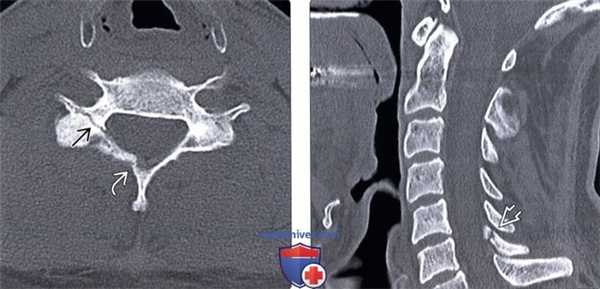

(Слева) КТ, аксиальный срез: односторонний перелом суставной колонны С6, распространяющийся на пластинку дуги.

(Справа) КТ, сагиттальный срез: у этого же пациента отмечается распространение перелома суставной колонны на одноименную пластинку дуги.